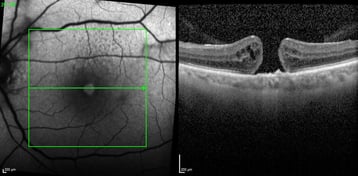

Das Makulaforamen ist ein Netzhautloch in der zentralen Stelle des schärfsten Sehens. Die Ursache ist häufig unbekannt, gelegentlich kann ein Makulaforamen nach einer Verletzung oder bei einer epiretinalen Gliose auftreten. Makulaforamen können unterschiedlich groß sein und unterschiedlich tief. Entsprechend können die Symptome variieren. In der Regel kommt es zu einem starken Abfall der Sehschärfe. Eine operative Versorgung ist bei großen Foramina die einzige Möglich, um eine Verbesserung der Sehschärfe zu erreichen. Bei sehr schlechter Ausgangssehschärfe ist der Erfolg aber oft begrenzt. Nichtsdestotrotz kann die Operation eine weitere Verschlechterung verhindern und den zentralen schwarzen oder gräulichen Bereich, den der Patient wahrnimmt, verkleinern.

Die Operation wird in der Augenklinik Nord Heidberg mittels minimalinvasiver 25 G-Technik durchgeführt, bei der nur 3 kleine Öffnungen mit 0,5 mm Durchmesser an der Außenseite des Auges angelegt werden müssen. Diese minimalinvasive Technik ermöglicht eine kurze Operationszeit, kurze stationäre Verweildauer und schnelle Rehabilitation des Patienten. In der Regel wird bei diesen Operationen eine Gasblase in das Auge eingegeben. Dies soll das Verschließen des Loches begünstigen. Nach der Operation empfehlen wir den Patienten, anfangs für mehrere Stunden am Tag den Blick gesenkt zu halten und das Auge wenig zu belasten, um den optimalen Operationserfolg sicherzustellen. Solange die Gasblase im Auge ist, bleibt die Sehschärfe noch stark reduziert, dies ist normal aufgrund der geänderten Brechkraft des Auges durch die Gasblase. Das Gas muss nicht separat entfernt werden. Der Körper resorbiert das Gas und ersetzt den inneren Augenbereich mit Flüssigkeit. Dieser Prozess kann je nach verwendetem Gas zwischen 1 und 8 Wochen dauern. In diesem Zeitraum dürfen keine Flugreisen oder Tauchgänge unternommen werden.